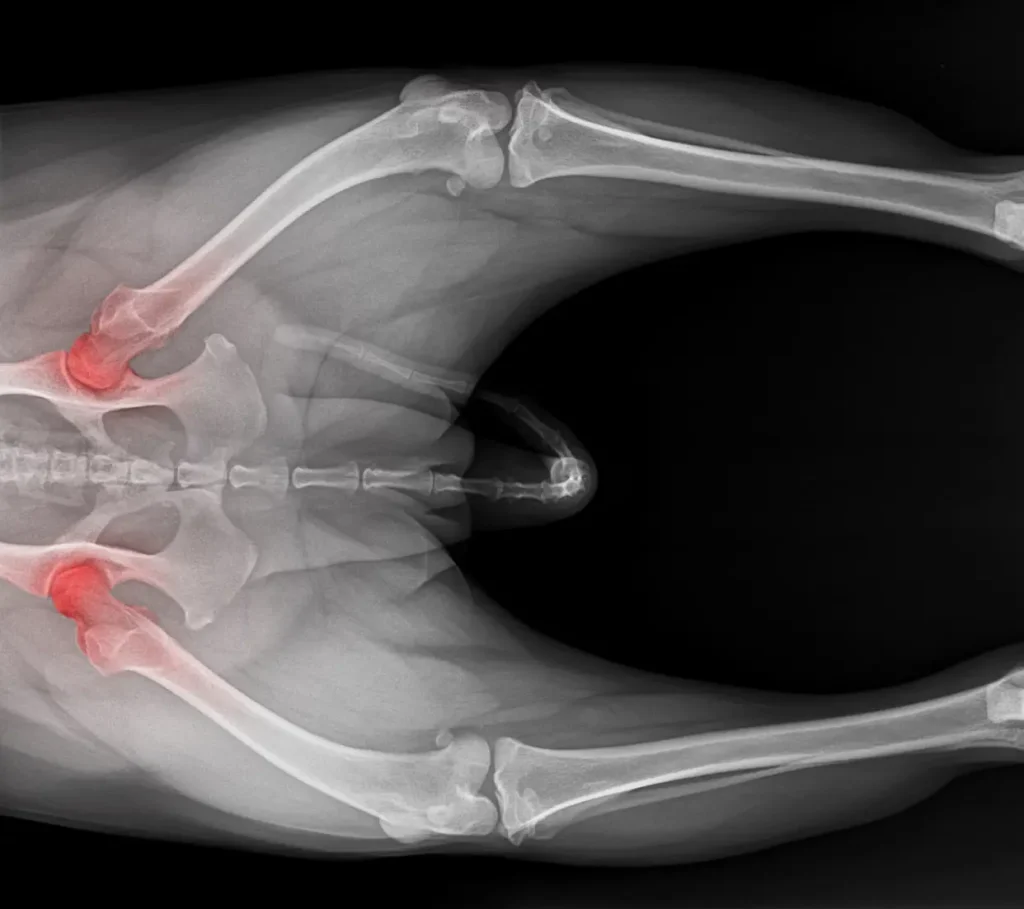

Wenn Sie eines oder mehrere der genannten Symptome bei Ihrem Hund feststellen, sollten Sie nicht zögern, einen Tierarzt aufzusuchen. Eine frühzeitige und exakte Diagnose ist der Schlüssel zu einer erfolgreichen Behandlung. Der Tierarzt wird durch eine gründliche orthopädische Untersuchung und bildgebende Verfahren wie Röntgenaufnahmen das Ausmaß der Arthrose feststellen und einen individuellen Behandlungsplan erstellen.

Arthrose, auch als degenerative Gelenkerkrankung oder Osteoarthritis bekannt, ist eine der häufigsten Ursachen für chronische Schmerzen bei Hunden, insbesondere im fortgeschrittenen Alter. Es handelt sich um einen schmerzhaften Verschleißprozess, der jedes Gelenk betreffen kann, am häufigsten jedoch Hüfte, Knie, Ellbogen und Wirbelsäule.

Gesunde Gelenke sind mit einer glatten Knorpelschicht überzogen, die wie ein Stoßdämpfer wirkt und reibungslose Bewegungen ermöglicht. Die Gelenkflüssigkeit (Synovia) schmiert das Gelenk zusätzlich. Bei einer Arthrose wird dieser schützende Knorpel durch Entzündungsprozesse und mechanische Abnutzung dünner und rauer. Im fortgeschrittenen Stadium kann der Knorpel so stark geschädigt sein, dass Knochen auf Knochen reibt. Der Körper versucht, diese Instabilität durch Knochenzubildungen (Osteophyten) am Gelenkrand zu kompensieren, was die Schmerzen und die Steifheit weiter verschlimmert.